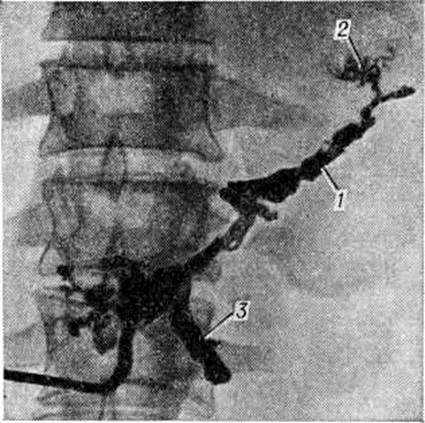

Охлаждение поджелудочной железы проводят путём локальной желудочной гипотермии (смотри полный свод знаний: Гипотермия искусственная, локальная) с помощью длительного промывания желудка холодной водой (открытый метод) или специальных охлаждающих аппаратов АГЖ-1 и другие (закрытый метод). Гипотермия позволяет в значительной мере подавить экскреторную функцию клеток железы. Однако длительность процедуры (4—6 часов), частое возникновение осложнений со стороны лёгких, выраженные нарушения кислотно-щелочного равновесия вследствие потерь желудочного сока при открытом методе ограничивают применение гипотермии в клинические, практике, особенно у больных пожилого и старческого возраста. С начала 70-х годы все более широкое применение для лечения острого Панкреатит находят различные цитостатики (5-фторурацил, циклофосфан, фторафур). Наиболее эффективно применение цитостатиков при регионарном введении в чревный ствол после катетеризации его по Сельдингеру — Эдману, что позволяет снизить дозу вводимого препарата, одновременно значительно повысив концентрацию его в тканях поджелудочной железы. По данным Джонсона (R. М. Johnson, 1972), А. А. Карелина и соавторами (1980), механизм лечебный действия цитостатиков при остром Панкреатит заключается в ингибировании экскреторной функции клеток поджелудочной железы. Экспериментальными исследованиями Ю. А. Нестеренко и сотрудники (1979) установлено, что внутриартериальное введение фторурацила в дозе 5 миллиграмм на 1 килограмм веса вызывает снижение внешне-панкреатической секреции на 91% и является оптимальной лечебный дозой. При внутривенном введении эта доза может быть увеличена в 2—3 раза. Применение цитостатиков показано при деструктивном Панкреатит Нецелесообразно их применение у больных с тотальным панкреонекрозом, гнойными осложнениями Панкреатит и почечно-печёночной недостаточностью. Выведение панкреатических ферментов и дезинтоксикация организма осуществляется с помощью методов внутривенного или внутриартериального введения диуретиков (для форсированного диуреза), перитонеального диализа и дренирования грудного лимфатических, протока. При форсированном диурезе панкреатические ферменты, компоненты кининовой системы, а также некоторые продукты клеточного распада выводятся почками. Методика форсированного диуреза включает водную нагрузку, введение диуретиков, коррекцию электролитного и белкового баланса. Основными компонентами вводимой жидкости могут быть 5—10% раствор глюкозы, раствор Рингера, реополиглюкин, солевой раствор. При внутривенном методе вводят ежесуточно 5—6 литров жидкости на протяжении 3—10 суток Форсирование диуреза осуществляют путём введения после инфузии каждых 2 литров жидкости мочегонных препаратов (лазикса, маннитола) и добиваются, чтобы суточный диурез достигал 3½—4 литров. По данным Г. А. Буромской и сотрудники (1980), внутриартериальное введение диуретиков более эффективно ликвидирует вне и внутриклеточную гидратацию, не повышает центральное венозное давление, не вызывает гиперволемию. В то же время при этом методе токсические продукты выводятся непосредственно из клеток поджелудочной железы, что обусловливает более выраженный дезинтоксикационный эффект. Объем вводимой внутриартериально жидкости зависит от интоксикации и степени дегидратации больного и составляет в среднем 4—5 литров в сутки. Продолжительность внутриартериального введения жидкости обычно составляет 3—4 суток При проведении форсированного диуреза необходим контроль за центральным венозным давлением, гематокритом, средним диаметром эритроцитов, показателями объёма циркулирующей крови, кислотно-щелочным равновесием, уровнем электролитов. Важную роль в борьбе с ферментативной токсемией играют антиферментные препараты (трасилол, контрикал, тзалол, пантрипин, гордокс и другие). Их необходимо вводить в больших дозах в течение 3—5 дней. Дренирование грудного лимфатических, протока (смотри полный свод знаний: Грудной проток) осуществляют при деструктивных формах панкреатита с целью выведения из организма ферментов поджелудочной железы. Количество удаляемой лимфы зависит от степени интоксикации и возможностей заместительной терапии. Лимфу, очищенную от токсических продуктов и панкреатических ферментов путём фильтрации через ионообменные колонки (смотри полный свод знаний: Лимфосорбция), реинфузируют в вену. По данным В. М. Буянова и сотрудники (1979), перспективным методом дезинтоксикации организма при остром Панкреатит является внутривенная жидкостная лимфостимуляция. Перитонеальный диализ (смотри полный свод знаний) показан при обнаружении в брюшной полости во время лапароскопии или лапаротомии большого количества серозного или геморрагического выпота. В зависимости от функции дренажей и состояния больного диализ продолжают 2—4 дня. Профилактику и лечение тромбоэмболических осложнений производят под контролем показателей тромбоз ластограммы и коагулограммы. При деструктивном Панкреатит уже в первые часы заболевания при наличии высокой фибринолитической активности и гипертрипсинемии для профилактики распространённого внутрисосудистого свёртывания крови целесообразно, кроме антиферментов, вводить также гепарин, низкомолекулярные растворы (5% раствор глюкозы, гемодез, реополиглюкин, поливинол, неокомпенсан и др.). Коррекцию электролитного обмена производят введением изотонического или 10% раствора хлорида натрия, 10% раствора хлорида калия, 1% раствора хлорида кальция, раствора Рингера — Локка и другие. При нарушении углеводного обмена вводят необходимые дозы глюкозы и инсулина. С целью коррекции белкового обмена переливают кровь, плазму, аминон, альбумин. Для профилактики гнойных осложнений, особенно в фазе расплавления и секвестрации некротических очагов в поджелудочной железе, применяют антибиотики широкого спектра действия (канамицин, гентамицин, мономицин, цепорин и другие). По данным В. С. Савельева (1977), наиболее эффективно введение антибиотиков в чрев-ный ствол. При некротических формах Панкреатит необходимо также стимулировать репаративные процессы в поджелудочной железе и других органах. Для этого назначают пентоксил, метилурацил, анаболические гормоны. Все операции при остром Панкреатит целесообразно разделять на три группы: 1) экстренные и срочные, выполняемые в первые часы и дни заболевания; 2) отсроченные, которые производят в фазе расплавления и секвестрации некротических очагов поджелудочной железы и забрюшинной клетчатки, через 10—14 дней и позднее от начала болезни; 3) плановые, выполняемые в период полного прекращения острого воспаления в поджелудочной железе, через 4—6 недель от начала приступа, после завершения обследования больного (эти операции предназначены для профилактики рецидива острого Панкреатит). Показания к экстренным и срочным операциям: разлитой ферментативный перитонит; острый Панкреатит, обусловленный холедохолитиазом (обтурацией большого сосочка двенадцатиперстной кишки). При экстренных и срочных операциях после лапаротомии через верхнесрединный разрез (смотри полный свод знаний: Лапаротомия) производят ревизию брюшной полости, выясняя состояние поджелудочной железы, забрюшинной клетчатки, париетальной брюшины и желчевыводящих путей. При отёчном Панкреатит в брюшной полости иногда обнаруживают серозный или желчный выпот. Поджелудочная железа увеличена в объёме, плотна на ощупь, на бледной или матовой поверхности её видны точечные кровоизлияния. При геморрагическом панкреонекрозе обнаруживаются кровянистый выпот, нередко с гнилостным запахом, часто с примесью желчи, при гнойном Панкреатит— мутный выпот с фибрином. Поджелудочная железа при ранней стадии геморрагического панкреонекроза увеличена, поверхность её покрыта множественными кровоизлияниями. При тотальном панкреонекрозе она бурого или чёрного цвета, на большом и малом сальнике, париетальной брюшине, брыжейке тонкой и толстой кишок и других органах часто видны очаги стеато-некроза. Выпот с примесью желчи, пропитывание ею печёночно-дуоденальной связки, увеличение размеров желчного пузыря, расширение общего желчного протока свидетельствуют о Панкреатит, осложнённом желчной гипертензией. При отёчном Панкреатит после удаления выпота брюшную полость обычно зашивают наглухо после обкалывания железы раствором новокаина с антибиотиками и антиферментными препаратами. При выраженной геморрагической или желчной имбибиции забрюшинной клетчатки производят широкое вскрытие забрюшинного пространства вокруг железы и в боковых каналах живота (около-ободочно-кишечных бороздах). Операцию заканчивают дренированием сальниковой сумки, иногда в сочетании с оментопанкреатопексией, или дренированием брюшинной полости с последующим перитонеальным диализом. При обширном геморрагическом панкреонекрозе А. А. Шалимов с сотрудники (1978), В. И. Филин с сотрудники (1979), Холлендер (L. F. Hollender, 1976) и другие производят резекцию поджелудочной железы, чаще всего левостороннюю. При остром Панкреатит, протекающем с желтухой, обусловленной холедохолитиазом, производят холедохотомию (смотри полный свод знаний), удаляют камни, заканчивая операцию наружным дренированием общего желчного протока (смотри полный свод знаний: Дренирование). При вклиненных камнях большого сосочка двенадцатиперстной кишки производят пластику большого сосочка двенадцатиперстной кишки — трансдуоденальную папиллосфинктеропластику (смотри полный свод знаний: Фатеров сосок). В фазе расплавления и секвестрации некротических очагов поджелудочной железы производят некрэктомию и секвестрэктомию. Некрэктомия возможна не ранее чем через 2 недель от начала заболевания, так как зона некроза железы чётко определяется не ранее 10-го дня с момента приступа острого Панкреатит Секвестрэктомия, то есть удаление отторгнувшихся некротизированных участков железы и забрюшинной клетчатки, возможна обычно не ранее 3—4-й недель от начала заболевания. Операция в фазе расплавления и секвестрации заключается в широком вскрытии сальниковой сумки через желудочно-ободочную связку, в ревизии железы и забрюшинной клетчатки, удалении некротизированных тканей, дренировании и тампонаде сальниковой сумки и забрюшинного пространства. После операции через дренажи осуществляют активную аспирацию гнойного отделяемого. Плановые операции направлены в основном на санацию желчного пузыря и протоков (холецистэктомия, холедохолитотомия, холедоходуоденостомия и другие) и лечение заболеваний других органов пищеварения, служащих причиной рецидива острого Панкреатит (язвенной болезни желудка, двенадцатиперстной кишки, дивертикулов двенадцатиперстной кишки, дуоденостаза и другие). В послеоперационном периоде продолжают комплексное консервативное лечение острого Панкреатит Тампоны из сальниковой сумки меняют на 7—8-й день, стараясь формировать широкий раневой канал, который периодически промывают антисептическими растворами (фурацилина, риванола, йодинола). В фазе секвестрации могут возникать аррозивные кровотечения. Иногда они могут быть обусловлены нарушениями свёртывающей системы крови. При профузных кровотечениях производят обшивание и перевязку сосудов в ране или на протяжении или их эмболизацию, тампонаду или резекцию поджелудочной железы. При фибринолитических кровотечениях показаны прямые гемотрансфузии (смотри полный свод знаний: Переливание крови) и введение ингибиторов фибринолиза — γ-аминокапроновой кислоты, антиферментов и другие Свищи поджелудочной железы возникают вследствие продолжающейся гнойной деструкции её или после операции по поводу панкреонекроза. В большинстве случаев при консервативном лечении, особенно при применении рентгенотерапии, свищи заживают в течение нескольких недель или месяцев. Если количество отделяемого из свища в течение 2—3 месяцев не уменьшается, показано оперативное лечение. Ложная киста поджелудочной железы также образуется вследствие локального некроза органа. При этом через разрушенные выводные протоки продолжается секреция панкреатического сока в очаг деструкции, который отграничивается вновь образуемой соединительной тканью, постепенно образующей стенку кисты. Псевдокиста поджелудочной железы может нагноиться, перфорировать или, сдавливая соседние органы, вызывать непроходимость кишечника, общего желчного протока. Методом выбора при оперативном лечении постнекротических псевдокист является панкреатоцистоэнтеро и панкреатоцистогастроанастомоз. При дистальном расположении кисты показана резекция поджелудочной железы; при нагноении кисты производят марсупиализацию (смотри полный свод знаний). ПрогнозПрогноз при остром Панкреатит всегда серьёзен. Общая летальность составляет от 3 до 7%, а летальность при панкреонекрозе — от 20 до 50%. В случаях панкреонекроза, потребовавших оперативного лечения, летальность колеблется от 30 до 85% . Отдалённые результаты лечения острого Панкреатит у 50% больных хорошие, более чем у 30% — удовлетворительные, у 15—20% развивается хронический Панкреатит. ПрофилактикаЦелесообразна диспансеризация больных, перенёсших острый Панкреатит Учитывая важную роль заболеваний желчных путей в возникновении острого Панкреатит, санация их является эффективной мерой профилактики рецидива заболевания. Необходимо также соблюдение диеты и исключение злоупотребления алкоголем. В период ремиссии рекомендуют санитарный-кур. лечение в санаториях желудочно-кишечные профиля (Боржоми, Железноводск, Трускавец, Краинка, Карлови Вари). Особенности острого панкреатита в пожилом и старческом возрастеПациенты пожилого и старческого возраста составляют более 25% больных острым Панкреатит Это объясняется прежде всего увеличением количества людей этого возраста среди населения. Немаловажное значение имеют также возрастные изменения в поджелудочной железе, в частности такие, как деформация протоков с облитерацией и расширением их, запустевание кровеносной капиллярной сети, фиброз междольковых перегородок и др. Способствуют более частому развитию острого Панкреатит и функциональный нарушения органов пищеварения, характерные для этого возраста, а также часто встречающиеся заболевания печёночных и желчных протоков, желудка, двенадцатиперстной и толстой кишок, сердечно-сосудистой системы. Наряду с обычной патоморфологические картиной заболевания у больных этой возрастной группы нередко наблюдается апоплексия поджелудочной железы или массивные жировые некрозы при липоматозе стромы железы. Клинические, проявления острого Панкреатит в этой группе больных характеризуются рядом особенностей. В связи с частым наличием у них разнообразных сопутствующих заболеваний даже лёгкие формы острого Панкреатит нередко протекают с выраженным нарушением функций жизненно важных органов и систем. Поэтому течение заболевания чаще сопровождается развитием острой сердечнососудистой, дыхательной, печёночно-почечной недостаточности, различных видов энцефалопатий и нарушением инкреторной функции поджелудочной железы. Это проявляется желтухой, олиго и анурией, гипо или гипергликемией. В то же время характерна незначительная болезненность при пальпации в надчревной области и выраженный парез желудочно-кишечные тракта. Комплексное консервативное лечение острого Панкреатит у больных пожилого и старческого возраста должно обязательно включать меры по лечению сопутствующих заболеваний, в первую очередь сердечно-сосудистой и дыхательной систем, профилактику и лечение печёночно-почечной недостаточности, нарушений углеводного обмена. В связи с этим лечение таких больных проводят в палате интенсивной терапии или реанимационном отделении. Особенности острого панкреатита у детейОстрый Панкреатит у детей встречается редко. Этиология заболевания весьма разнообразна (некоторые инфекционные болезни, аллергические состояния и др.). В большинстве случаев этиологического факторы остаются неясными; в связи с этим у детей внезапно возникающие острые Панкреатит принято называть идиопатическими. Заболевание часто начинается с общего недомогания ребёнка, отказа от пищи и подвижных игр. Развивающаяся затем клинические, картина в известной мере зависит от формы острого Панкреатит Острый отёк поджелудочной железы у детей (особенно младшей возрастной группы) протекает сравнительно легко, симптомы менее выражены, чем у взрослых, и часто расцениваются педиатрами как «интоксикация неясной этиологии». Проводимое симптоматическое лечение приводит к быстрому улучшению общего состояния. Только специальное обследование позволяет поставить правильный диагноз. У детей старшего возраста заболевание начинается с острых болей в животе, вначале разлитых, а затем локализующихся в надчревной области или носящих опоясывающий характер. Реже наблюдается постепенное нарастание болей. Одновременно появляются многократная рвота, обильное слюноотделение. Ребёнок принимает вынужденное положение, чаще на левом боку. Температура тела нормальная или субфебрильная, язык влажен, умеренно обложен белым налётом. Пульс удовлетворительного наполнения, ритмичен, учащён, АД нормальное или слегка понижено. При осмотре отмечается бледность кожных покровов. Живот правильной формы, не вздут, участвует в акте дыхания. Пальпация передней брюшной стенки безболезненна, живот мягкий. Такое несоответствие между жестокими болями в животе и отсутствием объективных данных, говорящих о наличии острого заболевания органов брюшной полости, характерно именно для отёчной формы острого Панкреатит В крови отмечается умеренный лейкоцитоз, без значительного изменения формулы. Наиболее информативным и ранним диагностическим признаком является повышение активности амилазы в крови. Несколько позже повышается содержание амилазы в моче. Как правило, наблюдается умеренная гипергликемия. Геморрагический и жировой некроз сопровождается выраженной симптоматикой и тяжёлым течением. У детей младшего возраста заболевание проявляется быстро нарастающим беспокойством. Ребёнок кричит и мечется от болей, принимает вынужденное положение. Постепенно двигательное беспокойство сменяется адинамией. Дети старшего возраста обычно указывают на локализацию болей в верхних отделах живота, их опоясывающий характер, иррадиацию в надключичную область, лопатку. Появляется многократная рвота, изнуряющая ребёнка. Общее состояние прогрессивно ухудшается. Кожные покровы бледны, с цианотичным оттенком. Развиваются эксикоз, тяжёлая интоксикация. Язык сухой, обложен. Пульс частый, иногда слабого наполнения, АД постепенно снижается. Температура тела обычно субфебрильная, в редких случаях повышается до 38-39°. При гнойном Панкреатит в начале заболевания ещё более выражено несоответствие между субъективными признаками острого живота и отсутствием или малой выраженностью объективных данных. Живот у ребёнка активно участвует в акте дыхания. Перкуссия и пальпация незначительно болезненны. Напряжение мышц передней брюшной стенки выражено слабо. Затем развивается парез кишечника, болезненность при пальпации усиливается, появляются симптомы раздражения брюшины. Температура тела повышается, характерен значительный лейкоцитоз. Наступает нарушение водно-электролитного баланса, повышается количество сахара в крови. Резко нарастает концентрация амилазы в крови и моче. Снижение её уровня является плохим прогностическим признаком. Иногда у детей младшего возраста тяжёлый геморрагический или жировой некроз проявляется клинические, картиной острого прогрессирующего асцита. Рентгенологические исследование у детей, как правило, мало информативно. У детей старшего возраста при обоснованном подозрении на панкреонекроз можно применить лапароскопию. Дифференциальный диагноз острого Панкреатит у детей проводят с острым аппендицитом, кишечной непроходимостью и перфорацией полых органов. Лечение острого Панкреатит у детей преимущественно консервативное. Всем детям после установления диагноза назначают комплекс лечебный мероприятий, направленных на борьбу с болевым синдромом, интоксикацией и вторичной инфекцией. Важной задачей является создание функциональный покоя поджелудочной железы, блокада её ферментообразующей функции, борьба с нарушениями водноэлектролитного баланса. Комплексное консервативное лечение у детей при остром Панкреатит, диагностированном в ранние сроки (1—2-е сутки), обычно приводит к выздоровлению. При чётких клинические, признаках гнойного Панкреатит или перитонита показано оперативное вмешательство. У детей дошкольного возраста сложность дифференциальной диагностики часто приводит к необходимости распознавать острый Панкреатит во время лапаротомии, производимой по поводу предполагаемого острого аппендицита или другого заболевания. Оперативное лечение проводят по тем же принципам, что и у взрослых. Все дети, переболевшие острым Панкреатит, нуждаются в длительном (до 2 лет) диспансерном наблюдении у хирурга и эндокринолога. Хронический панкреатитХронический Панкреатит встречается часто — по секционным данным, от 0,18 до 6% случаев. Однако в клинические, практике это заболевание, по-видимому, встречается ещё чаще, но не всегда диагностируется. Обычно хронический Панкреатит выявляется в среднем и пожилом возрасте, несколько чаще у женщин, чем у мужчин. Хронический Панкреатит у детей встречается редко. Различают первичный хронический Панкреатит, при котором воспалительный процесс с самого начала локализуется в поджелудочной железе, и так называемый вторичный, или сопутствующий, Панкреатит, постепенно развивающийся на фоне других заболеваний желудочно-кишечные тракта, например, язвенной болезни, гастрита, холецистита и другие. Этиология и патогенезЭтиология первичного хронический Панкреатит разнообразна. В хронический форму может перейти тяжёлый или затянувшийся острый Панкреатит Но чаще хронический Панкреатит возникает постепенно под воздействием таких факторов, как бессистемное нерегулярное питание, частое употребление острой и жирной пищи, хронический алкоголизм, особенно в сочетании с дефицитом в пище белков и витаминов. По данным Бенсона (J. A. Benson), в США хронический рецидивирующий Панкреатит в 75% случаев возникает у больных, страдающих хронический алкоголизмом. Пенетрация язвы желудка или двенадцатиперстной кишки в поджелудочную железу также может привести к развитию хронический воспалительного процесса в ней. Среди других этиологического факторов следует назвать хронический нарушения кровообращения и атеросклеротическое поражение сосудов поджелудочной железы, инфекционные болезни, экзогенные интоксикации. Иногда Панкреатит возникает после операций на желчных путях или желудке. Более редкой причиной является поражение поджелудочной железы при узелковом периартериите, тромбоцитопенической пурпуре, гемохроматозе, гиперлипемии. В ряде случаев, по данным некоторых исследователей, в 10—15% причина хронический Панкреатит остаётся неясной. Предрасполагающими факторами в возникновении хронический Панкреатит являются также препятствия для выделения панкреатического сока в двенадцатиперстную кишку, вызванные спазмом или стенозом ампулы сфинктера Одди, а также недостаточностью его, которая облегчает попадание дуоденального содержимого в проток поджелудочной железы. Одним из ведущих механизмов развития хронический воспалительного процесса в поджелудочной железе является задержка выделения и внутриорганная активация панкреатических ферментов, в первую очередь трипсина и липазы (фосфолипазы А), осуществляющих аутолиз паренхимы железы. Активация эластазы и некоторых других ферментов ведёт к поражению сосудов поджелудочной железы. Действие кининов на мельчайшие сосуды приводит к развитию отёка. Гидрофильный эффект продуктов распада в очагах некроза ткани поджелудочной железы также способствует отеку, а в последующем — образованию ложных кист. В развитии, особенно прогрессировании хронический воспалительного процесса, большое значение имеют процессы аутоагрессии. При хронический гастрите (смотри полный свод знаний) и дуодените (смотри полный свод знаний) нарушается выработка энтерохромаффинными клетками слизистой оболочки желудка и двенадцатиперстной кишки полипептидных гормонов, которые участвуют в регуляции секреции поджелудочной железы. При хронический Панкреатит инфекционные происхождения возбудитель может проникнуть в поджелудочную железу из двенадцатиперстной кишки (например, при дисбактериозе, энтеритах) или из желчных путей (при холецистите, холангите) через протоки поджелудочной железы восходящим путём, чему способствуют дискинезии желудочно-кишечные тракта, сопровождающиеся дуоденопанкреатическим и холедохопанкреатическим рефлюксом. Патологическая анатомияПатологоанатомически хронический Панкреатит подразделяют на хронический рецидивирующий Панкреатит и хронический склерозирующий Панкреатит Хронический рецидивирующий Панкреатит по существу является пролонгированным вариантом острого мелкоочагового панкреонекроза, поскольку всякий рецидив болезни сопровождается образованием свежих очагов некроза паренхимы поджелудочной железы и окружающей жировой клетчатки. Макроскопически в период обострения железа представляется несколько увеличенной в объёме и диффузно уплотнённой. Микроскопически в ней обнаруживаются свежие и организующиеся очаги некроза паренхимы и жировой клетчатки, чередующиеся с рубцовыми полями, очагами обызвествления, мелкими псевдокистами, лишёнными эпителиальной выстилки. Отмечается также значительная деформация и расширение просвета выводных протоков, содержащих уплотнённый секрет и нередко микролиты. В ряде случаев наблюдается диффузно-очаговое обызвествление интерстиция, и тогда говорят о хронический кальцифицирующем Панкреатит Воспалительная инфильтрация из лейкоцитов наблюдается лишь в очагах свежего некроза паренхимы. Она постепенно стихает по мере организации очагов деструкции, сменяясь диффузно-очаговыми инфильтратами из лимфоидных, плазматических клеток и гистиоцитов. Многие исследователи считают эти инфильтраты проявлением аутоиммунной реакции замедленного типа, возникающей в ответ на постоянное антигенное воздействие из очагов деструкции ацинусов. Хронический склерозирующий Панкреатит отличается диффузным уплотнением и уменьшением поджелудочной железы в размерах. Ткань железы приобретает каменистую плотность и макроскопически напоминает опухоль. Микроскопически обнаруживают диффузный фокальный и сегментарный склероз с прогрессирующим разрастанием соединительной ткани вокруг протоков, долек и внутри ацинусов. Причиной склероза является постоянная убыль паренхимы, протекающая по типу некроза или атрофии отдельных ацинусов и групп ацинусов. В далеко зашедших случаях на фоне диффузного фиброза с трудом обнаруживаются небольшие островки атрофичной паренхимы. Наряду с этим отмечается выраженная пролиферация эпителия протоков с образованием аденоматозных структур, которые иногда трудно дифференцировать с аденокарциномой. В просветах расширенных выводящих протоков постоянно встречаются сгущённый секрет, кристаллические отложения извести, микролиты. В окружности протоков обнаруживается большое количество гиперплазированных панкреатических островков (Лангерганса). Новообразования ацинусов не происходит, некроз паренхимы железы замещается рубцом. Как и при рецидивирующей форме Панкреатит, среди полей фиброзной ткани можно обнаружить лимфоплазмоцитарные инфильтраты, являющиеся отражением аутоиммунных процессов. При этом морфологически в поджелудочной железе преобладают не некротические, а дистрофически-атрофические изменения ацинусов с медленным их замещением соединительной тканью. При всех вариантах хронический Панкреатит наблюдаются одинаковые осложнения. Чаще всего встречается рубцовая стриктура протока поджелудочной железы, а также закупорка его камнем или аденоматозным полипом. При этом возможна обтурация общего желчного протока с развитием механической желтухи. Иногда наблюдается тромбоз селезёночной вены. Нередко на фоне хронический Панкреатит развивается сахарный диабет, хотя в отличие от ацинусов островки Лангерганса хорошо регенерируют, и среди рубцовой ткани их всегда можно обнаружить. Клиническая картинаКлиническая картина хронический Панкреатит весьма вариабельна, но в большинстве случаев включает следующие симптомы: боль в надчревной области и левом подреберье; диспептические явления; так называемый панкреатогенные поносы; похудание, гипопротеинемию, симптомы полигиповитаминоза; признаки сахарного диабета. Боль локализуется в надчревной области справа (при преимущественной локализации процесса в области головки поджелудочной железы); при вовлечении в воспалительный процесс её тела боль наблюдается в надчревной области; при поражении её хвоста — в левом подреберье. Нередко боль иррадиирует в спину (на уровне X—XII грудных позвонков) или имеет опоясывающий характер, усиливается в положении больного лёжа на спине и может ослабевать в положении сидя, особенно при небольшом наклоне вперёд. Боль может иррадиировать также в область сердца, имитируя стенокардию, в левую лопатку, левое плечо, а иногда в левую подвздошную область. Интенсивность и характер болей различны; они могут быть постоянными (давящими, ноющими), появляться через некоторое время после еды (как при язвенной болезни), особенно после приёма жирной или острой пищи, или быть приступообразными по типу панкреатической колики. Диспептические симптомы (панкреатическая диспепсия) встречаются часто, особенно при обострении заболевания или тяжёлом течении болезни. Многие больные отмечают также потерю аппетита, отвращение к жирной пище. В то же время при развитии сахарного диабета больные могут ощущать сильный голод и жажду. Часто наблюдаются повышенное слюноотделение, отрыжка, тошнота, рвота, метеоризм. Стул в лёгких случаях нормальный, в более тяжёлых наблюдается склонность к поносам или чередование запоров и поносов. Однако в типичных далеко зашедших случаях хронический Панкреатит (при наличии явных признаков внешнесекреторной недостаточности поджелудочной железы) более характерными являются панкреатические поносы с выделением обильного кашицеобразного зловонного с жирным блеском кала. Вследствие развития внешнесекреторной недостаточности поджелудочной железы и нарушения процессов переваривания и всасывания в кишечнике нарастает похудание. Ему способствует обычно наблюдавшаяся у больных потеря аппетита, а также присоединение сахарного диабета. При тяжёлых формах заболевания возможны депрессия, ипохондрия и другие психические нарушения. При алкогольном Панкреатит нарушения психики могут быть обусловлены длительным действием алкоголя на центральная нервная система Течение заболевания обычно имеет затяжной характер. Выделяют 5 форм заболевания: 1) рецидивирующая форма, характеризующаяся отчётливыми периодами ремиссии и обострений процесса; 2) болевая форма, протекающая с постоянными болями, доминирующими в клинической картине; 3) псевдоопухолевая форма; 4) латентная (безболевая) форма; 5) склерозирующая форма, для которой характерны рано возникающие и прогрессирующие признаки недостаточности функций поджелудочной железы. При последней форме иногда наблюдается механическая желтуха вследствие сдавления общего желчного протока склерозированной головкой поджелудочной железы. Т. Г. Ренева с сотрудники (1978) выделяет 3 формы течения хронический Панкреатит: лёгкую, среднетяжёлую и тяжёлую. Последняя протекает с упорными поносами, дистрофическими расстройствами, нарастающим истощением. ОсложненияОсложнения: кисты, кальцификаты поджелудочной железы, сахарный диабет, тромбоз селезёночной вены, стеноз протока поджелудочной железы. На фоне длительного хронический Панкреатит возможно развитие рака поджелудочной железы. ДиагнозФизикальное исследование. При пальпации живота у больных хронический Панкреатит обычно характерна болезненность в надчревной области и левом подреберье. Рядом исследователей описаны болевые точки и зоны, болезненность в которых особенно характерна. Так, при поражении головки поджелудочной железы боль может отмечаться при давлении в так называемый панкреатической точке Дежардена, располагающейся в области проекции на переднюю брюшную стенку дистального отдела протока поджелудочной железы (приблизительно на расстоянии 5—7 сантиметров от пупка по линии, соединяющей пупок с правой подмышечной впадиной), или в более широкой холедохо-панкреатической зоне Шоффара, располагающейся между указанной выше линией, передней срединной линией тела и перпендикуляром, опущенным на последнюю линию из точки Дежардена. Нередко отмечается болезненность точки в реберно-позвоночном углу (симптом Мейо-Робсона). Иногда отмечается зона кожной гиперестезии соответственно зоне иннервации 8 — 10-го грудного сегмента слева (симптом Кача) и некоторая атрофия подкожной клетчатки в области проекции поджелудочной железы на переднюю брюшную стенку, описанная А. А. Шелагуровым (1970). Пропальпировать увеличенную и уплотнённую поджелудочную железу при хронический Панкреатит удаётся очень редко. Некоторое диагностическое значение может иметь аускультация надчревной области при полном выдохе: иногда слышен систолический шум, который возникает вследствие сдавления брюшной части аорты увеличенной и уплотнённой поджелудочной железой. Лабораторные методы исследования нередко выявляют у больных хронический Панкреатит умеренную гипохромную анемию, ускорение РОЭ, нейтрофильный лейкоцитоз, диспротеинемию за счёт повышенного содержания глобулинов, повышение активности трансаминаз и альдолазы в сыворотке крови. При поражении островкового аппарата поджелудочной железы выявляется гипергликемия (смотри полный свод знаний) и гликозурия (смотри полный свод знаний), однако для выявления лёгких степеней нарушения углеводного обмена необходимо исследование сахарной кривой с двойной нагрузкой глюкозой (смотри полный свод знаний: Углеводы, методы определения). При нарушениях внешнесекреторной функции поджелудочной железы обычно выявляется более или менее выраженная гипопротеинемия; в более тяжёлых случаях — нарушение электролитного обмена, в частности гипонатриемия (смотри полный свод знаний). Определение в дуоденальном содержимом, а также в крови и моче содержания ферментов поджелудочной железы позволяет дать оценку функциональный состояния органа. В дуоденальном содержимом, полученном с помощью двухканального зонда (смотри полный свод знаний: Дуоденальное зондирование), до и после стимуляции поджелудочной железы секретином и панкреозимином определяют общее количество сока, его бикарбонатную щёлочность, содержание трипсина, липазы и амилазы; в крови — содержание амилазы, липазы, антитрипсина; в моче — амилазы. Одновременное проведение исследования содержания панкреатических ферментов в дуоденальном соке, крови, а также амилазурии позволяет значительно точнее отразить состояние внешнесекреторной функции поджелудочной железы у больных хронический Панкреатит, чем раздельное проведение этих исследований в разные дни. Гиперамилазурия, достигающая при хронический Панкреатит иногда цифр 2048— 4096 единиц (по Вольгемуту), выявляется чаще, чем гиперамилаземия, однако увеличение амилазы мочи (до 256—512 единиц) иногда наблюдается и при других заболеваниях органов брюшной полости. Содержание ферментов в крови и моче повышается в период обострения Панкреатит, а также при препятствиях к оттоку панкреатического сока (воспалительный отёк головки железы и сдавление протоков, рубцовый стеноз большого сосочка двенадцатиперстной кишки и другие). В дуоденальном содержимом концентрация ферментов и общий объем сока в начальном периоде болезни могут быть несколько увеличенными, однако при выраженном атрофически-склеротическом процессе в железе эти показатели снижаются. Копрологическое исследование (смотри полный свод знаний: Кал) выявляет повышенное содержание в кале непереваренной пищи (стеаторея, креаторея, амилорея, китаринорея). По мнению Осте да (W. J. Austad, 1979), стойкая стеаторея при хронический II. появляется тогда, когда внешняя секреция поджелудочной железы снижается не менее чем на 90%. Рентгенодиагностика. При рентгенологическое исследовании желудочно-кишечные тракта обнаруживают в случае увеличения поджелудочной железы смещение желудка кверху и кпереди, расширение дуоденальной петли и уплощение медиального контура нисходящей части двенадцатиперстной кишки (рисунок 1). С помощью релаксационной дуоденографии (смотри полный свод знаний: Дуоденография релаксационная) на этом контуре можно выявить короткие ригидные участки, ряд заострённых углублений в виде игл (спикул), вдавления по краям большого сосочка двенадцатиперстной кишки. На обзорных снимках поджелудочной железы определяют также камни или отложения солей кальция (рисунок 2), а на компьютерных томограммах обнаруживают расширенный и деформированный проток поджелудочной железы. При холеграфии (смотри полный свод знаний) иногда находят сужение дистального отдела общего желчного протока. Большое значение в диагностике хронический Панкреатит имеет эндоскопическая ретроградная холангиопанкреатография (смотри полный свод знаний: Панкреатохолангиография ретроградная). В начале заболевания протоки поджелудочной железы не изменены или отмечается деформация мелких выводных протоков поджелудочной железы. В дальнейшем эти протоки сужаются, часть их облитерирована, а в других — могут определяться мелкие кистоподобные расширения. Просвет протока поджелудочной железы становится неравномерным, на стенках его появляются неровности и в давления. В случае формирования абсцессов и псевдокист контрастное вещество из разрушенных протоков проникает в паренхиму железы и обрисовывает в ней полости, позволяя уточнить их положение и величину. В отличие от псевдокист в абсцессах могут при этом выявляться некротические массы. При целиакографии можно выделить две формы хронический Панкреатит Для первой формы типичны увеличение поджелудочной железы, её гиперваскуляризация и негомогенное контрастирование в паренхиматозной фазе (рисунок 3). Вторая форма более характерна для Панкреатит с выраженными фиброзными изменениями в поджелудочной железе. Она отличается смещением и сужением сосудов и обеднением сосудистого рисунка. Паренхиматозная фаза отсутствует или ослаблена. При всех формах Тилени Арнешьё(H. Tylen, В. Arnesjo, 1973) наблюдали стенозы крупных артерий вне поджелудочной железы — собственной печёночной, гастродуоденальной, селезёночной. Контуры суженных участков оставались ровными, в то время как при раке поджелудочной железы они имели «изъеденный» характер. Псевдокисты выглядят как округлые аваскулярные образования, смещающие прилежащие артериальные ветви. Во время операции и в послеоперационном периоде (если в протоках поджелудочной железы или полости кисты оставлен катетер для дренажа) для уточнения состояния протоков можно провести панкреатографию (смотри полный свод знаний). Если после операции по поводу кисты образовался наружный или внутренний свищ поджелудочной железы, целесообразно проведение фистулографии (смотри полный свод знаний), которая позволяет охарактеризовать свищевой ход и остаточную полость кисты (рисунок 4). Радиоизотопное сканирование поджелудочной железы с меченным селеном-75 метионином также имеет определённое диагностическое значение. Эхография позволяет выявить наличие, характер и протяжённость морфологический изменений в поджелудочной железе. Дифференциальный диагноз часто очень труден. Хронический Панкреатит необходимо дифференцировать прежде всего с опухолью поджелудочной железы (смотри полный свод знаний); при этом большое значение имеют методы инструментальной диагностики: целиакография, эндоскопическая ретроградная холангиопанкреатография, компьютерная томография, эхография и радиоизотопное сканирование поджелудочной железы. Дифференциальный диагноз проводят также с желчнокаменной болезнью (смотри полный свод знаний), язвенной болезнью желудка и двенадцатиперстной кишки, хронический энтеритом и другие.